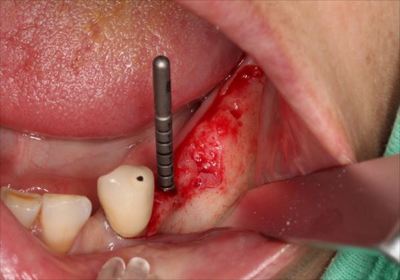

いつものようにパイロットドリルで安全域までドリリングして角度の確認を行います。

![]()

予定通りの角度にドリリングできていますのでドリルステップを進めます。